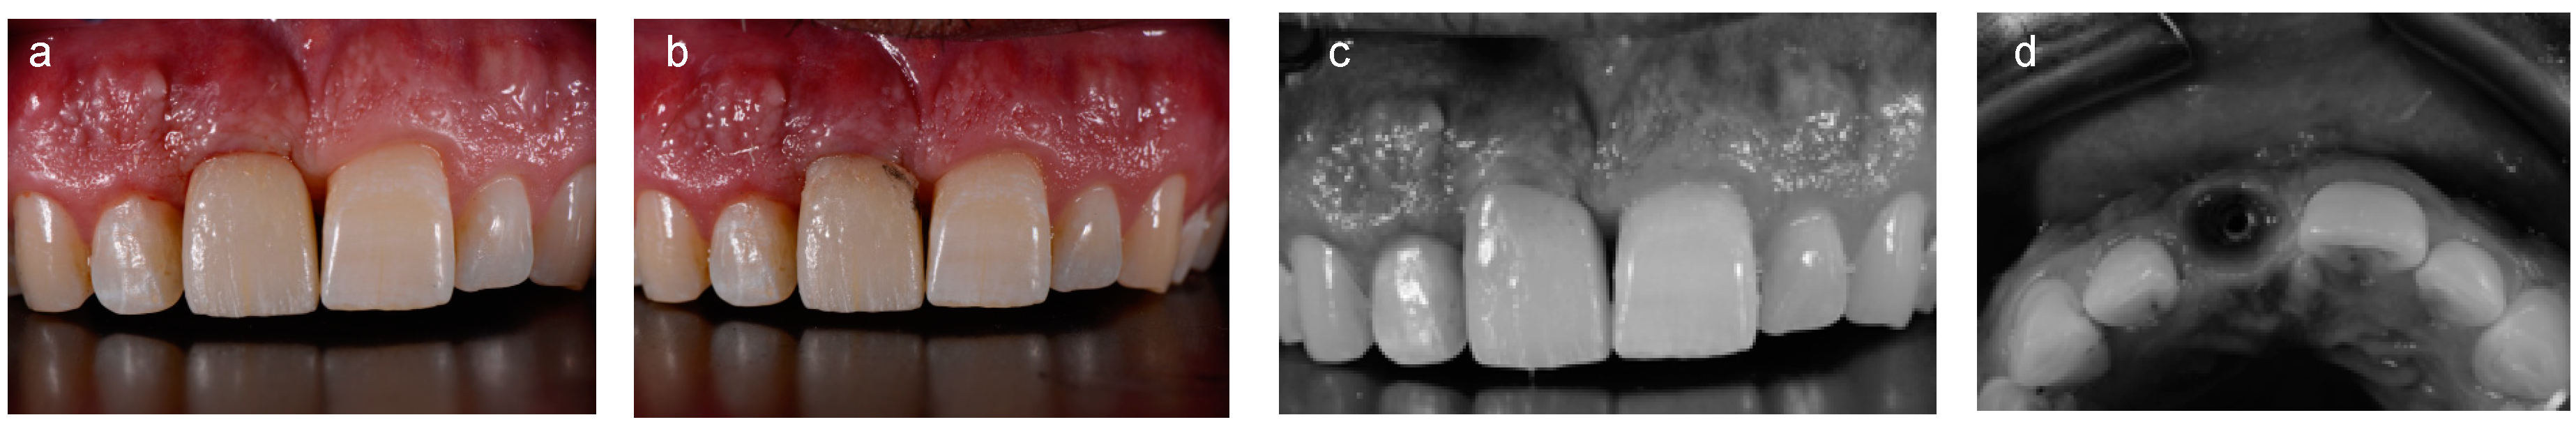

2.3. Digital Work-Flow

- Dental arch with the cemented provisional crown,

- Provisional crown connected with a digital analogue,

- Dental arch with a scan body screwed onto the implant.